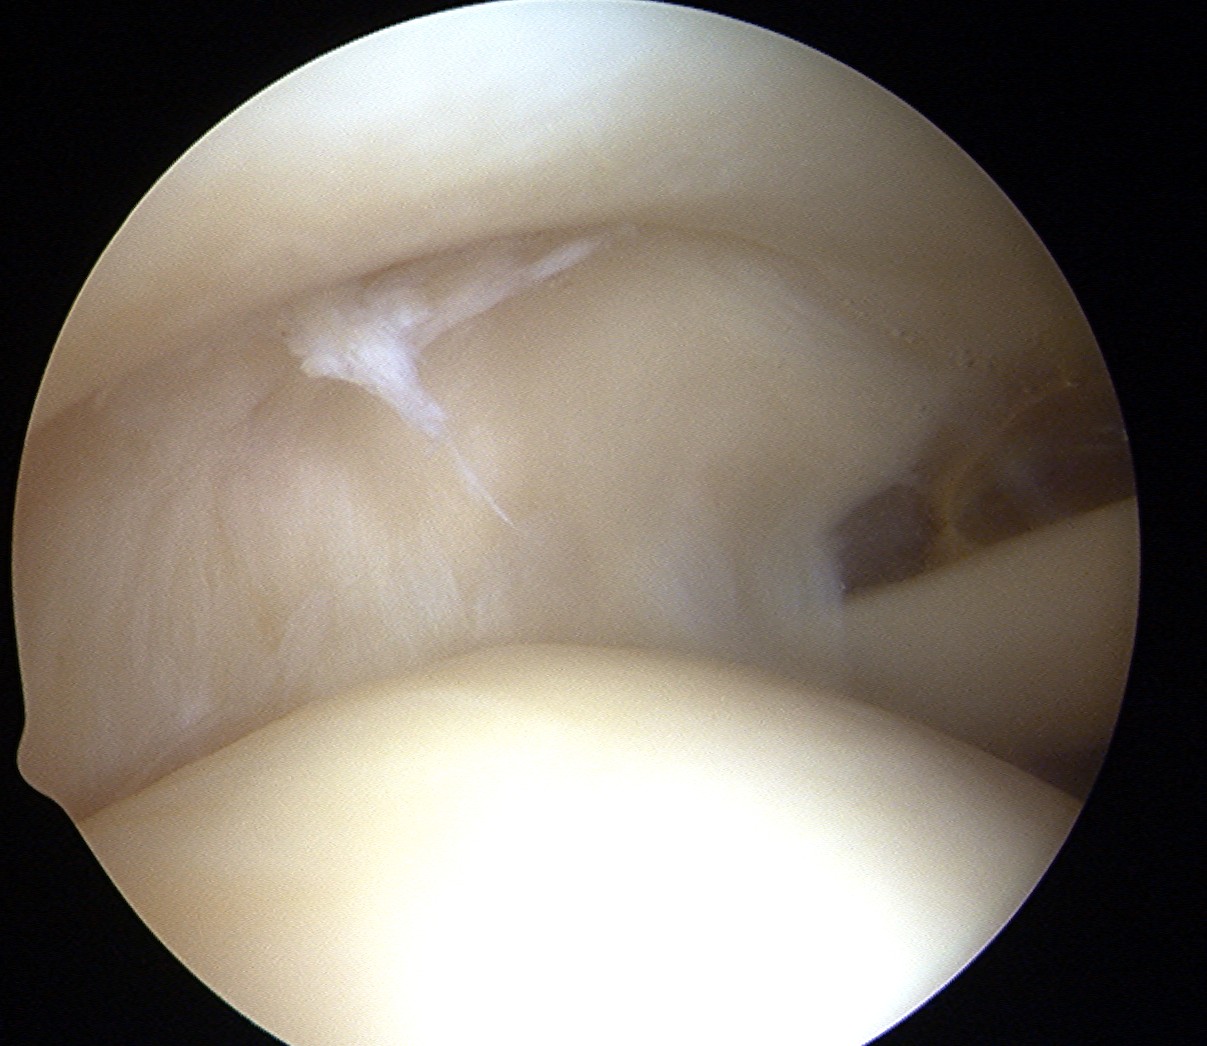

Subacromial space

Portals

| Posterior | Lateral subacromial portal |

Redirect posterior portal Under acromion |

Midportal clavicle |

| Usually viewing portal |

Rotator cuff repair / Subacromial decompression Distal clavicle resection |